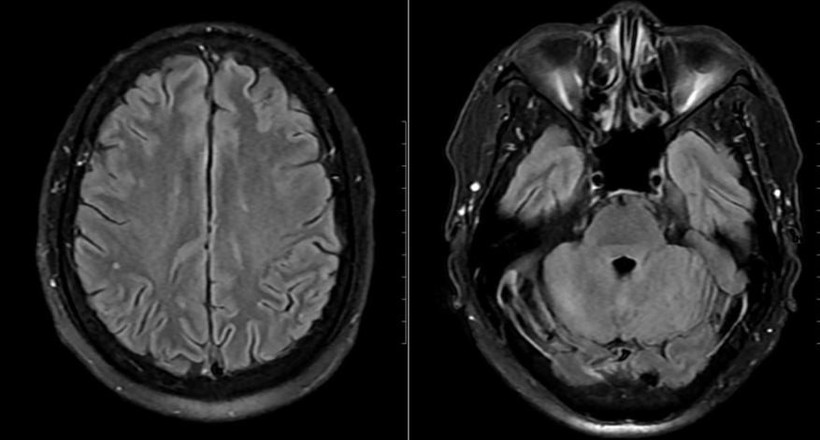

Hình ảnh chụp tổn thương não của bệnh nhân.

Mặc dù chưa có biểu hiện thần kinh rõ ràng, bệnh nhân vẫn được chọc dò dịch não tủy để loại trừ biến chứng. Kết quả cho thấy dịch não tủy có tăng tế bào và protein, phản ứng Pandy dương tính, xác định viêm não-màng não. Bên cạnh đó, hình ảnh MRI sọ não phát hiện ổ tổn thương nhỏ tại thùy chẩm trái.